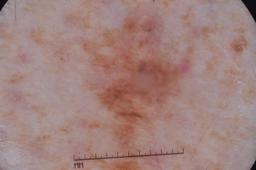

ISIC-DICM-17K (ISIC Dermoscopic Images and Clinical Metadata 17K) is a curated and balanced dataset derived from the International Skin Imaging Collaboration (ISIC) Archive Gallery. It comprises 17,060 dermoscopic images and clinical metadata (8,530 melanoma and 8,530 non-melanoma classes).

For more details, please follow the project’s GitHub repository: https://github.com/mmu-dermatology-research/isic-dicm-17k

This dataset was used in this study and benchmark to explore the effectiveness of multimodal learning for skin lesion classification:

S. Ahammed, X. Cui, W. Lu and M. H. Yap, "Skin Lesion Classification using Dermoscopic Images and Clinical Metadata: Insights from Multimodal Models," 2025 IEEE/CVF Conference on Computer Vision and Pattern Recognition Workshops (CVPRW), Nashville, TN, USA, 2025, pp. 222-230, DOI: 10.1109/CVPRW67362.2025.00027